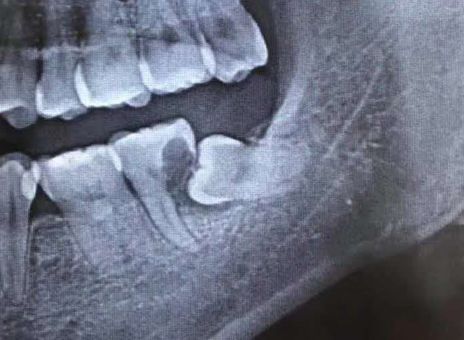

患者張先生2個(gè)月前突然發(fā)現(xiàn),自己下頜左側(cè)牙齒,遇涼、熱都會劇烈疼痛,甚至不敢用左側(cè)牙齒吃東西,在某口腔門診鉆開牙齒,反復(fù)換藥治療幾次后仍未見緩解,才想著到大醫(yī)院看一看。二一五醫(yī)院口腔科接診后發(fā)現(xiàn),患者口內(nèi)下頜最后一顆牙齒上有溢出的白色充填材料,而這顆患牙在幾次不當(dāng)治療后,已經(jīng)明顯松動,且咬合時(shí)劇烈疼痛,患者自述在前期治療過程中沒拍X線片明確病情,接診醫(yī)師隨即為他安排了口腔CT拍攝。CT發(fā)現(xiàn),在這“搖搖欲墜”的牙齒下,還悄悄隱藏著一顆傾斜的智齒,而這顆智齒,已經(jīng)幾乎“吃光了”它側(cè)方“松動”牙齒的牙根,這才是導(dǎo)致張先生牙疼反復(fù)治療無效的根本原因!